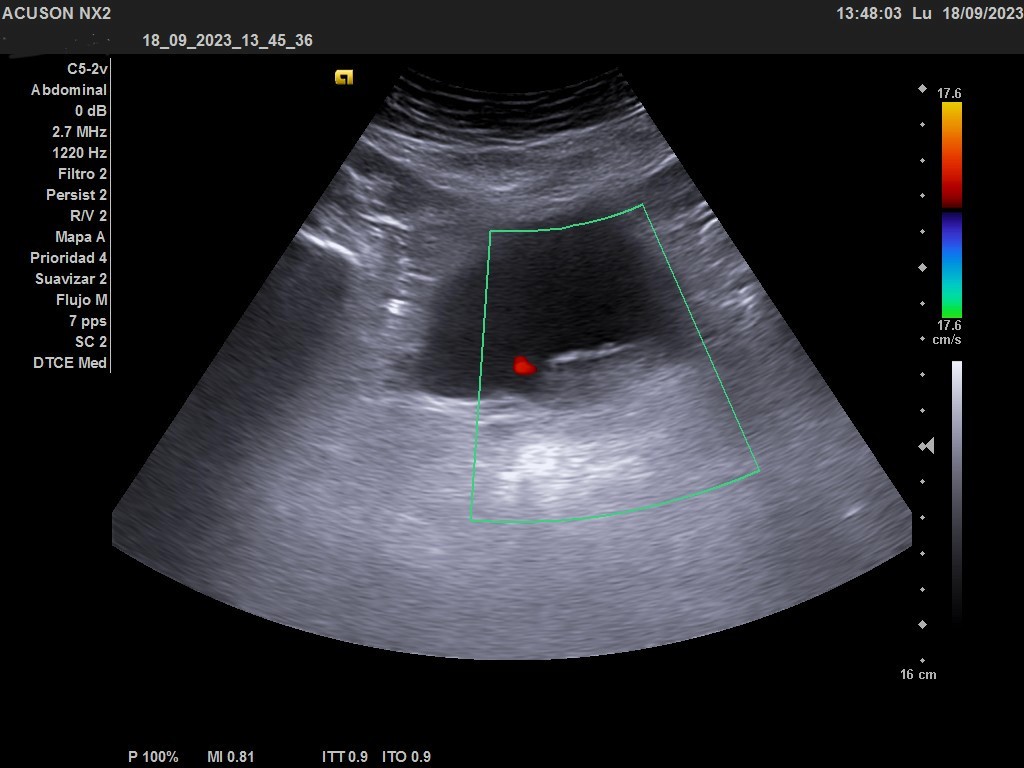

Ecografía clínica urológica: vejiga moderadamente replecionada. Se visualiza en pared posterior imagen hiperecogénica que no capta al Doppler color, de características sospechosas de malignidad. Riñones sin alteraciones en parénquima ni signos de hidronefrosis.

En la ecografía urológica reglada ambos riñones son de tamaño normal y parénquima conservado. La vejiga está replecionada, pero se identifica un engrosamiento nodular de 26 x 15 mm en la pared inferolateral izquierda, próxima al meato. Próstata de pequeño tamaño con un volumen de 7 cc.